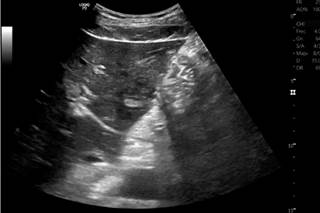

On the first day of hospitalization, an attempt was made to extract the foreign body percutaneously, which was unsuccessful. The patient was then taken for a laparotomy with intraoperative ultrasound to mark the abscess and locate the foreign body. The abscess was successfully drained, and the fish bone was removed (Figures 3, 4 and 5) through a single incision in the liver with minimal bleeding. Hemostatic hepatorrhaphy was subsequently performed using chromic catgut suture with a BP1 atraumatic needle, and a drainage system was left in place. Cultures from the secretion isolated Streptococcus constellatus, a bacterium that is part of the oropharyngeal flora and was sensitive to the empirically initiated antibiotics. In-hospital antibiotic therapy was administered for five days, followed by outpatient treatment to complete a 21-day course. Prior to discharge, an ultrasound showed resolution of the liver abscess and recent postoperative changes in the left lobe (Figure 6).